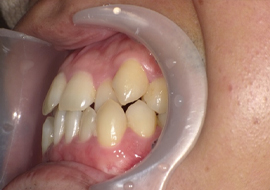

症例6

Before

After

| 主訴 | 噛み合わせが気になる |

|---|---|

| 年齢 | --- |

| 治療 期間 |

約2年11ヶ月 |

| 治療 内容 |

インビザラインコンプリヘンシブ 右上6番・左上6番ALLセラミッククラウン |

| 治療費 | ¥1,116,000(税込)/調整料含む |

| 治療のリスク | 歯を動かすことで、歯茎が下がるリスクある。 矯正終了後は、リテーナーを使用し、後戻りを防ぐ必要がある。 |